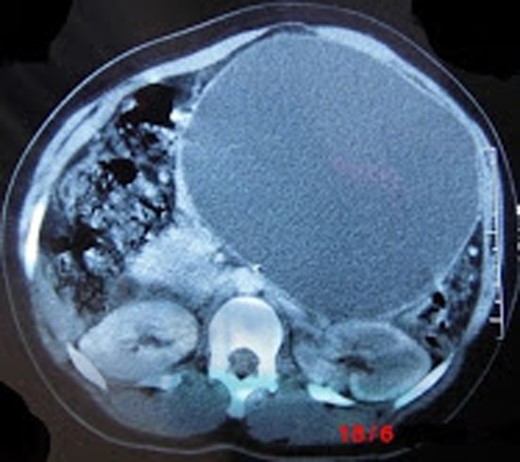

A 27-year-old African woman who is non-alcoholic presented with an enlarging epigastric mass of 8-year duration following blunt abdominal trauma from a fall off a motorbike. This mass persisted despite percutaneous aspiration. Apart from post-prandial bloating, early satiety and difficulty while lying supine, she was clinically well. Physical examination revealed a tense, forward bulging, epigastric mass of ∼20 cm diameter with a palpable smooth upper border but impalpable lower border. The mass did not move with respiration as it appeared fixed to the retroperitoneum. There was no organomegaly nor palpable lymphadenopathy. Blood tests revealed a raised serum amylase of 151 U/L (normal 70–300 U/L) and a haemoglobin level of 11 g/dl (normal 12–15). A computed tomography (CT) scan confirmed a retroperitoneal cystic mass within the body and tail of pancreas with the main differential diagnosis of a pancreatic pseudocyst (Fig. 1). The patient consented for an internal drainage of the pseudocyst. Under general anaesthesia, a nasogastric tube was passed because gastric emptying is often impaired. Following an upper midline incision, the lesser sac was entered through the gastrocolic omentum and the large, tense, smooth thick-walled mature cyst of ∼25 cm in diameter was found attached to the body and tail of the pancreas. It bulged inferiorly into the transverse mesocolon causing a localized dilatation (Fig. 2). A laparotomy revealed a normal gall bladder and excluded gallstones as a possible cause of the pancreatitis. Taking care to avoid vessels densely adherent to the pseudocyst, a 5-cm incision of the anterior wall of the cyst with cutting diathermy drained ∼2.8 l of thick creamy fluid consistent with pancreatic juice. Loculi within the cyst were broken down with the suction catheter (Fig. 3). As malignancy was not suspected, a sample was not analysed. The upper end of a retrocolic Roux loop of jejunum with its closed end was approximated to the front of the cyst without tension (Fig. 4). A generous side-to side two - layer anastomosis between the opening into the cyst and a longitudinal jejunostomy was fashioned. This entailed an inner ‘all coats’ continuous suture of non-absorbable material (nylon) and an outer layer of interrupted absorbable (vicryl) to ensure serosal apposition (Fig. 5). Intestinal continuity was restored by jejunojejunostomy at the base of the Roux loop. The mesocolic and jejunojejunal defects were closed to avoid internal hernias. The distended transverse colon was decompressed by suction aspiration of colonic gas using a 22-g i.v. cannula through the taenia so as to allow a safe abdominal closure. The patient lost ∼200 ml of blood and received a unit of whole blood intraoperatively. Following abdominal lavage, a corrugated (R) paracolic drain was inserted and the midline wound closed by a mass closure technique with a monofilament non-absorbable 1.0 nylon, and interrupted nylon sutures for the skin. A dry dressing was applied. Postoperative recovery was uneventful. The nasogastric tube was removed on the second day as her serum amylase was within the normal range. Her bowels moved on the second day and the drain removed on the fifth postoperative day. The patient was discharged on the 10th postoperative day and long-term follow-up planned.

CT showing a large pancreatic pseudocyst in the body and tail of pancreas bulging into the anterior abdominal wall and displacing loops of the small bowel.